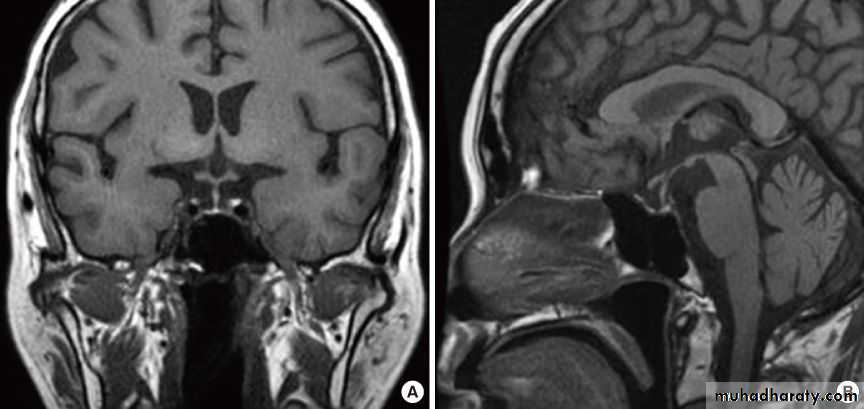

Computed tomography or magnetic resonance imaging of the pituitary fossa and formal visual field testing should be arranged in cases of suspected prolactinoma.

The tumors most often associated with amenorrhea include craniopharyngiomas , germinomas ,gliomas, and metastatic lesions.

The most common of these tumors, craniopharyngiomas.

prolactinoma(benign adenomas of lactotrophs) is the commonest adenoma causing amenorrhea.

Found in 1/3 of women with secondary amenorrhea